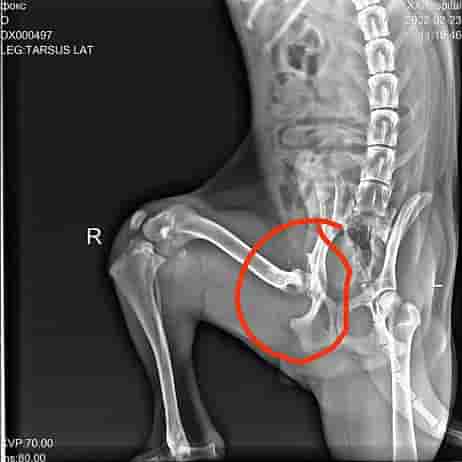

Всём привет. У нас новый подопечный, зовут его Фокс, по возрасту примерно месяцев 10. Фокса высадили из машины на базе Подольска, просто тупо выкинули, скорее всего из за его проблемы с лапкой. Сотрудники базы это увидели по камерам наблюдения и связались с нами.

И вот у Фокса новая страничка в жизни и она начинается с испытания. Проблема с тазобедренным суставом. Пока он ещё молодой и идёт рост нужно принимать решение, потом при закостенении сустава это будут сильные боли.

Сделали рентген, проконсультировались с несколькими хирургами и приняли решение. 19 марта 2022 года будет операция.